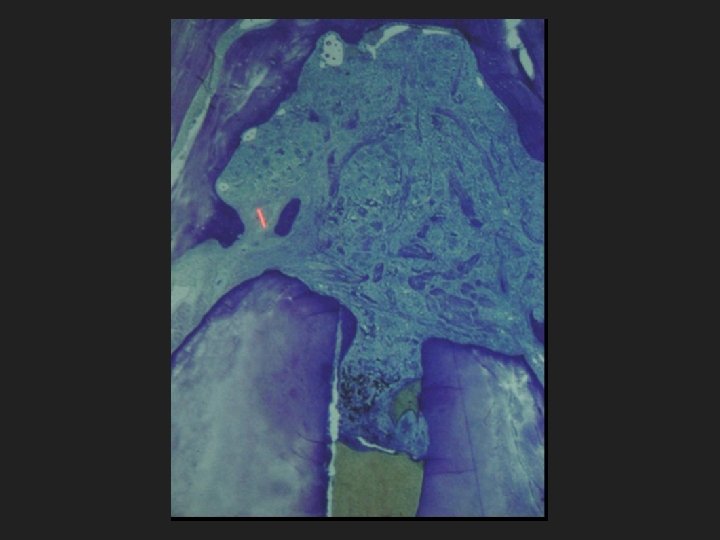

Estudio de Kakehashi OOO, 1965 Pulpas expuestas con bacterias Inflamación crónica. lesiones periapicales, granulomas y quistes Pulpas expuestas Libres de bacterias “germ-free” Mínima inflamación pulpar, formación de puente dentinario

BIOFILME

Microbial status of apical root canal system of human mandibular first molars with primary apical periodontitis after “one-visit” endodontic treatment. Nair, Stéphane Henry, Victor Cano, Jorge Vera. OOOO, 2005.